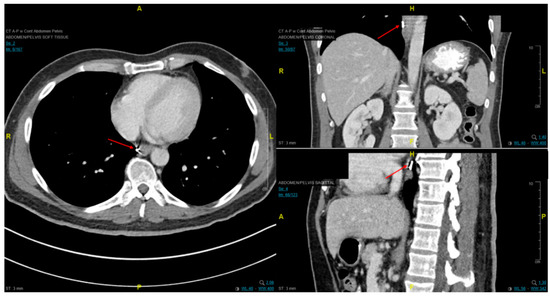

Fiducial markers can be placed endoscopically to delineate the extent of disease with high technical success with a small risk of migration [79][80][81]. Stable fiducial markers improve the reliability of target volume delineation and assessment of respiratory tumor motion with four-dimensional CT (4D-CT) simulation as a direct visual correlate of tumor extent. Combined with fused PET/CT, fiducials reduce the margins for treatment planning due to improved confidence of accurately defined gross tumor volumes (GTVs) [82] and facilitate daily image-guided radiation therapy (IGRT) during treatment [83], see Figure 7 and Figure 8. Moreover, 4D-CT imaging at simulation has a greater benefit in GEJ and gastric tumors due to the propensity of respiratory motion [84] and aids in internal target volume construction and planning target volume expansions during treatment planning. Radiation treatments generally are conventionally fractionated (1.8–2.0 Gy daily); however, previously mentioned SIB techniques treating at 2.2–2.25 Gy daily can push dose to gross disease past 60 Gy. If given sequential neoadjuvant chemotherapy, the extent of original disease is often included in the clinical target volume receiving 4500–5040 cGy and boost is only directed to residual gross disease. Clinical target volumes extend 3–4 cm craniocaudal and 1 cm radially and are edited off anatomical structures that are clinically uninvolved such as vertebral bodies, trachea, aorta, lung, and pericardium. For middle and upper thoracic tumors, the at-risk periesophageal and adjacent mediastinal lymph nodes and, for distal esophageal and GEJ tumors, the celiac lymph nodes are covered. Multi-institutional consensus contouring guidelines for IMRT in esophageal and gastroesophageal tumors have been published [85].

Figure 7. Axial, coronal, and sagittal CT images demonstrating EUS-placed fiducial (red arrow) proximal to esophageal tumor.